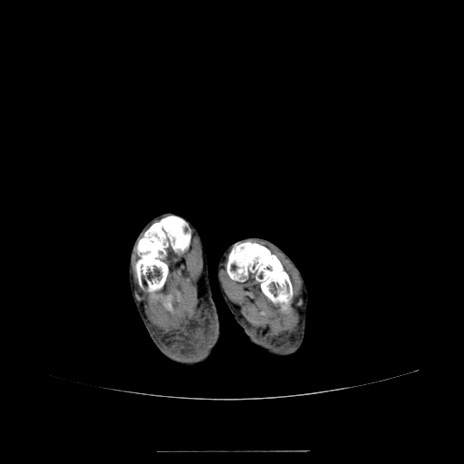

冠状断像

【症例】70歳代女性

【主訴】お腹が張る

【現病歴】1週間くらい前から腹部膨満の自覚あり。昨日夜から増悪したため、本日救急外来受診。

【身体所見】意識清明、BT 36.5℃、BP 165/106mmHg、HR 80bpm、SpO2 98%、腹部:膨満、軟、自発痛・圧痛なし、触診にて不快感あり、腸蠕動音:減弱

【データ】WBC 12600、CRP 1.04